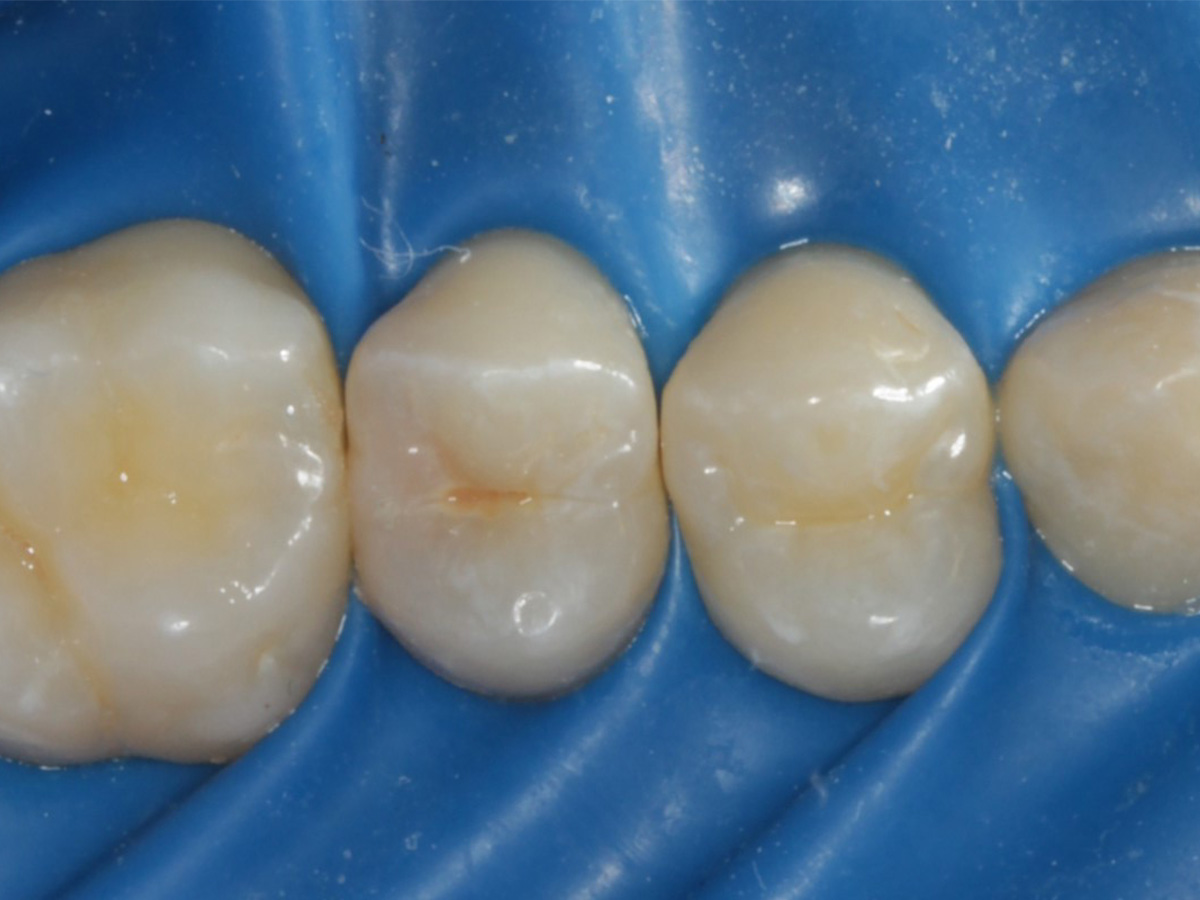

Abbildung 2

Intakte Kaufläche